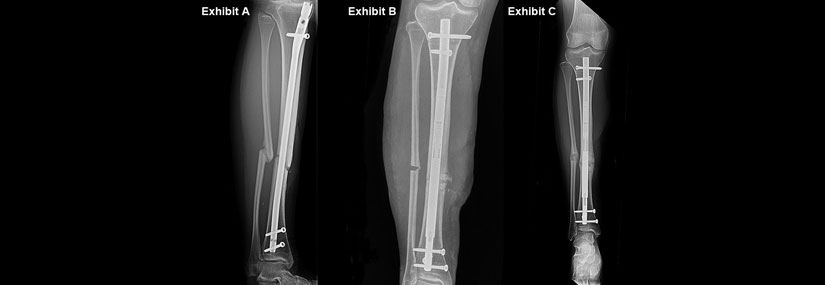

Non-Unions Malunion

Non-union and malunion are complications that can arise from fractures or bone surgeries. Both conditions affect the proper healing and alignment of bones. Here's a detailed overview of each:

Non-Union

Non-union occurs when a fractured bone fails to heal properly within the expected time frame, typically 6 to 9 months after the injury.

Malunion

Malunion occurs when a fractured bone heals in an incorrect position or alignment, leading to functional impairment or deformity.